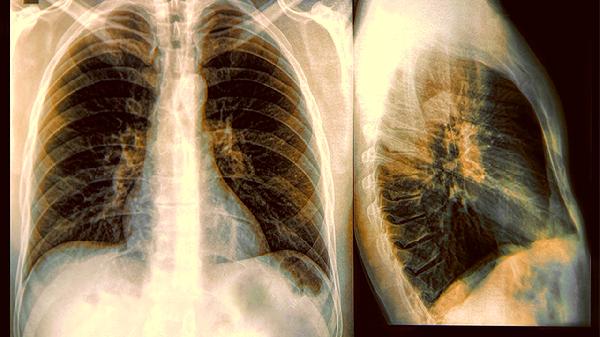

常规胸片对小于1厘米的结节识别率低,部分磨玻璃样结节在X光下几乎隐形。这也是为何临床建议高危人群改用低剂量螺旋CT筛查。